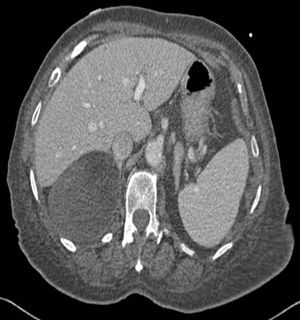

Image IQ: 85-year-old Male, History of Aortic Stenosis ByDuke Duncan, MDApril 2nd 201585-year-old male with history of aortic stenosis receiving contrast-enhanced CT for preoperative evaluation.